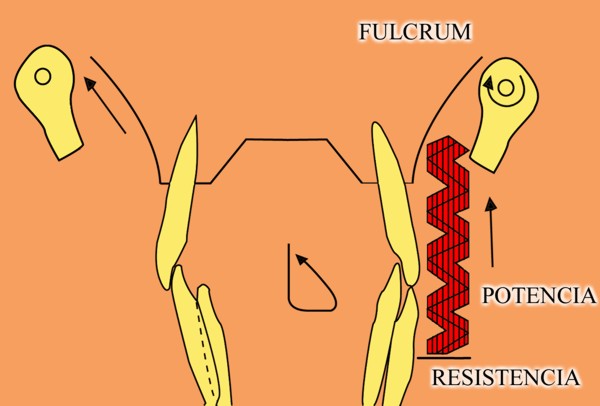

En un esquema de lateralidades a la izquierda, observamos que el Fulcrum de la misma lo encontramos en el cóndilo izquierdo, Cóndilo de Trabajo, la Potencia se encuentra en la fuerza generada por el Pterigoidéo Ext. del lado derecho, Cóndilo de No Trabajo, y la resistencia se dispone, en el caso de una FUNCIÓN DE GRUPO, en las Crestas Triangulares Internas de la tabla premolar-molar superior, que rozan contra las Crestas Centrales antagonistas ,correspondientes al inferior.

Por lo tanto, el Brazo de Potencia se establece entre el CnT(POTENCIA),y el CT(Fulcrum), mientras que los Brazos de Resistencia de las distintas piezas que intervienen en la Función de Grupo, se encuentran entre estas piezas y el CT(Fulcrum).

Como podemos ver en el esquema, estos son menores que el Brazo de Potencia y por lo tanto la fuerza generada por el mismo, producirá mayor deterioro , pues la palanca no está equilibrada:

EL BRAZO DE POTENCIA ES MAYOR QUE EL DE RESISTENCIA (Fig.6)